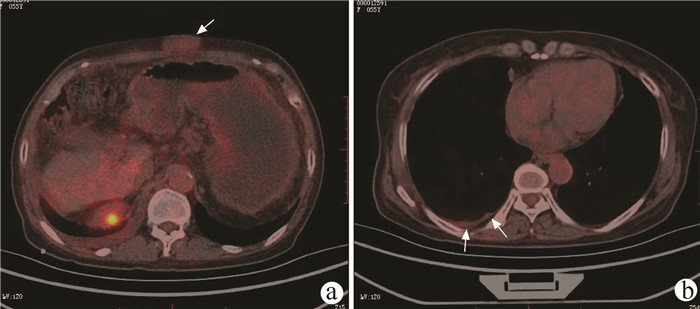

Malignant pleural mesothelioma with peritoneal metastasis in cirrhotic decompensation: A case report

Lixia LU, Xiaoqing XIE, Ying ZHENG, Xin LIU, Jianping WANG, Junke WANG, Pan WANG, Xiaohui YU

2022, 38(2): 418-419. DOI: 10.3969/j.issn.1001-5256.2022.02.030

Abstract(880) HTML (255) PDF (2461KB)(43)

Abstract: